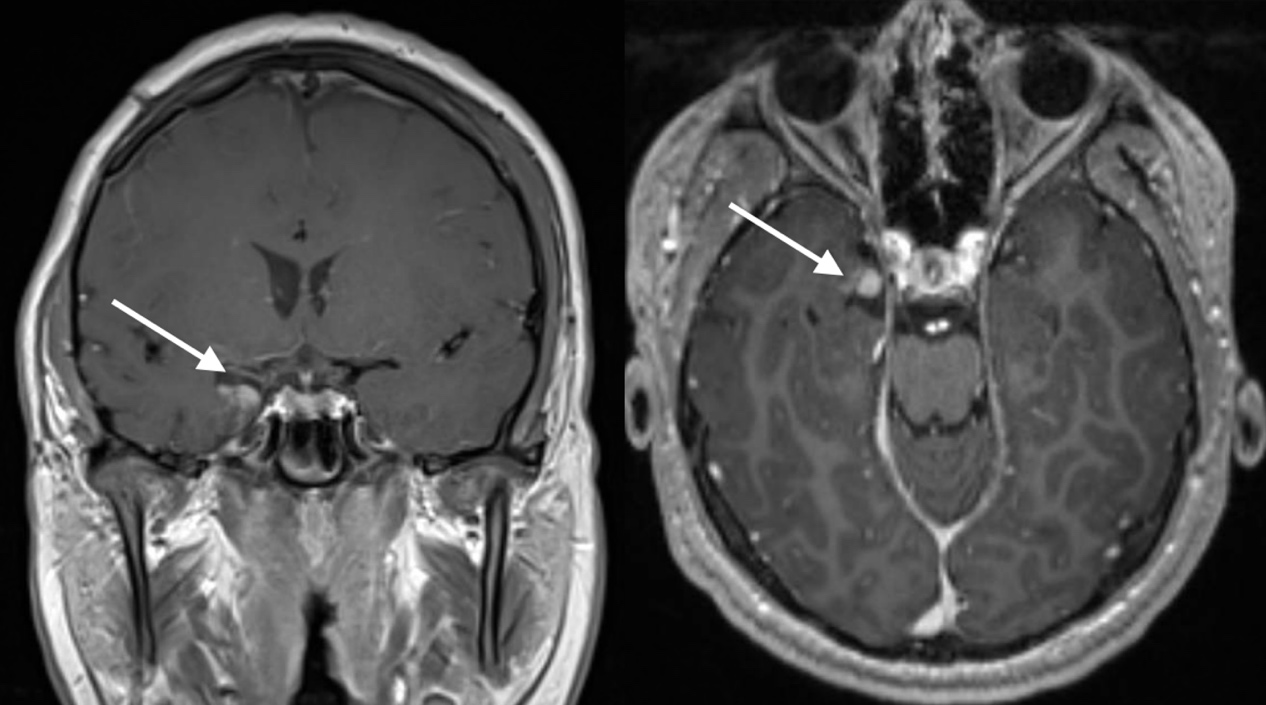

术前影像

Jimmy一开始接受外科手术时只有7岁,内侧颞叶肿瘤使他在复杂部分癫痫发作时会出现严重的意识障碍和精神症状,他会短暂地失去意识,四肢抽搐,还会不断重复自己癫痫发作前的动作,流口水、吞咽、走路等,这些使他无法正常生活和学习,因此选择接受外科手术。他的父母慕名求诊于INC旗下国际神经外科顾问团(WANG)专家成员、国际儿童神经外科专家James T. Rutka教授,教授行经侧裂入路为其行切除手术,术后7年均未发作。